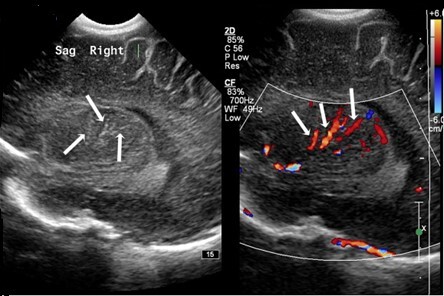

Neonatology Lenticulostriate Vasculopathy 1 Image